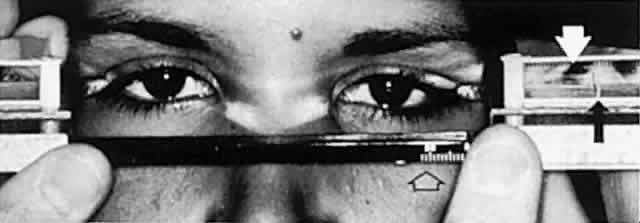

and white adults. Am J Ophthalmol 98:438, 1984 16. Musch DC, Frueh BR, Landis JR: The reliability of Hertel exophthalmometry. Observer variation between

physician and lay readers. Ophthalmology 92:1177, 1985 17. Cline RA, Rootman J: Enophthalmos: a clinical review. Ophthalmology 91:229, 1984 18. Miller MT, Spencer MA: Progressive hemifacial atrophy. A natural history study. Trans Am Ophthalmol Soc 93: 203, 1995 19. Soparkar CNS, Patrinely JR, Cuaycong MJ et al: The silent sinus syndrome: a cause of spontaneous enophthalmos. Ophthalmology 101:772, 1994 20. Bullock JD, Bartley GB: Dynamic proptosis. Am J Ophthalmol 102:104, 1986 21. Allen SJ, Naylor D: Pulsation of the eyeballs in tricuspid regurgitation. Can Med Assoc J 133:119, 1983 22. Stephens KF, Reinecke RD: Quantitative forced ductions. Trans Am Acad Ophthalmol Otolaryngol 71:324, 1967 23. Gamblin GT, Harper DG, Galentine P et al: Prevalence of increased intraocular pressure in Graves' disease. Evidence